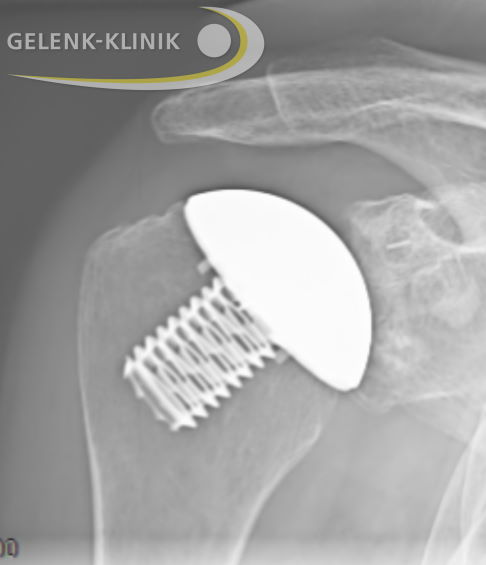

Röntgenbild einer Schulterprothese: Kappenprothese mit Pfannenersatz aus Kunststoff. Dabei bleibt die ursprüngliche Anatomie erhalten, die verschlissenen Gelenkflächen werden sowohl auf Seite des Oberarmkopfes (Humeruskopf) als auch auch an der Pfanne ersetzt. Sehnen und Bänder bleiben erhalten. © Gelenk-Klinik

Die Sehnen und die grundlegende Anatomie des ursprünglichen Gelenks werden bei der Operation einer Kappenprothese beibehalten. Der Spezialist ersetzt nur die zerstörten Gelenkflächen, indem er am Oberarmkopf eine metallische Kappe aufsetzt. Die abgenutzte Pfanne erneuert er durch ein Polyethylen-Inlay. Gleichzeitig entfernt der Operateur störende Knochenanbauten, damit die Metallkappe optimal auf dem Polyethylen-Inlay gleiten kann. Der Halbkugel-ähnliche Charakter der Kappe ermöglicht den Betroffenen einen hohen Bewegungsumfang.

Knochensparender Ersatz der Gelenkflächen von Oberarmkopf und Gelenkpfanne mithilfe einer Kappenprothese. Dieses Modell der Schulterprothese erhält die ursprüngliche Anatomie der Schulter. Die Glenoidkomponente aus Kunststoff ist im Röntgen kaum sichtbar. © Gelenk-Klinik